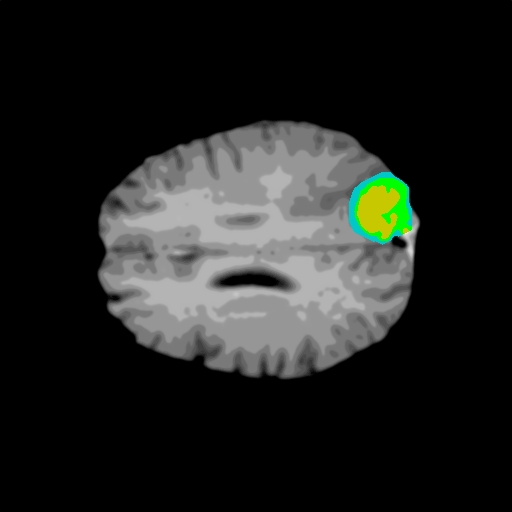

Extensive experiments have been performed in the current setup, and experimental outcomes are reported with the demonstration of numerical and statistical analyses using the proposed QFS-Net, QIS-Net [39], convolutional U-Net [18] and Residual U-Net (URes-Net) architectures [20]. The human expert segmented skull-tripped contrast enhanced DSC brain MR input image slices of size and ROIs are provided in Figure 5 as samples. The demonstration of QFS-Net segmented images followed by the essential post-processed outcome on the slice no. for class level with four distinct activation schemes () are shown in Figure 6. It is evident from the experimental data provided in Table LABEL:tab1 that the proposed QFS-Net performs optimally for the -connected quantum fuzzy pixel information heterogeneity assisted activation () with and gray scale set in comparison with other thresholding schemes and gray scale sets under the four evaluation parameters () [44]. The segmented tumors obtained using the proposed self-supervised procedure under class transition levels with four different thresholding schemes , , and are demonstrated in Figures 7- 8 for the class boundary sets and [39], respectively. The segmented images using the remaining two class boundary sets ( and ) [39] are provided in the supplementary materials section. The segmented ROIs describing the whole tumor region after the masking procedure using QIS-Net, U-Net and URes-Net are also reported in Figure 9.